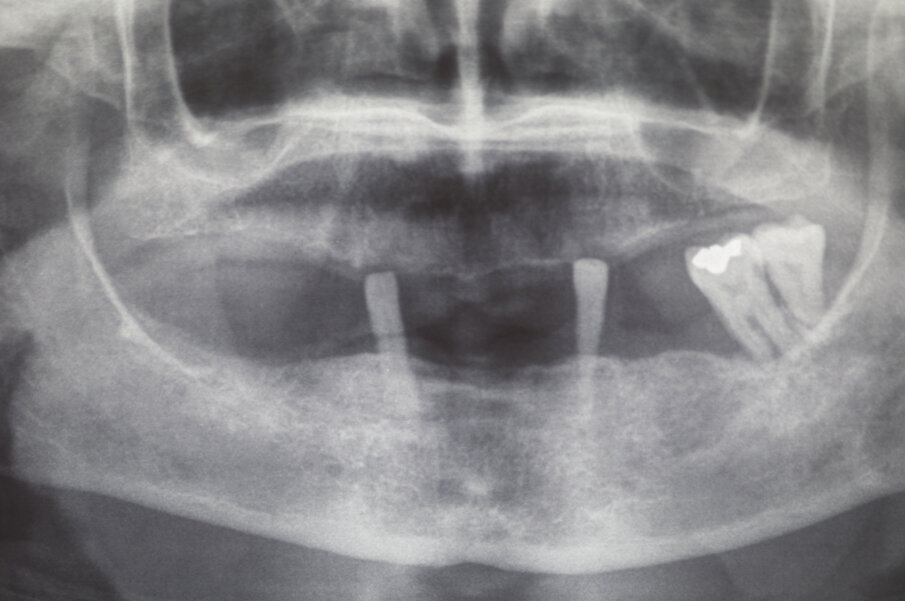

La paziente A. S. di anni 67 si presentata in visita richiedendo la sostituzione della protesi totale superiore con una nuova protesi, possibilmente fissa (Figg. 1-3). Essendo l’anamnesi negativa si è proceduto allo studio e alla pianificazione del caso. La paziente si è presentata con una OPT delle arcate dentarie (Fig. 4) che evidenziava un’ottima quantità di osso alveolare residuo. Dopo esame intra- orale si prescrive una CBCT per poter pianificare nel dettaglio la chirurgia implantare.

Verificata la precisione del lavoro si procede alla consegna. La Fig. 38 evidenzia la perfetta salute dei tessuti peri-implantari a protezione dei MUA, e nelle figure 39 e 40 evidenziano l’ottimo adattamento del manufatto finale ai tessuti intra ed extra-orali. La panoramica di controllo a 12 mesi dal completamento del lavoro evidenzia una perfetta stabilità dei livelli ossei dopo il carico protesico (Fig. 41).